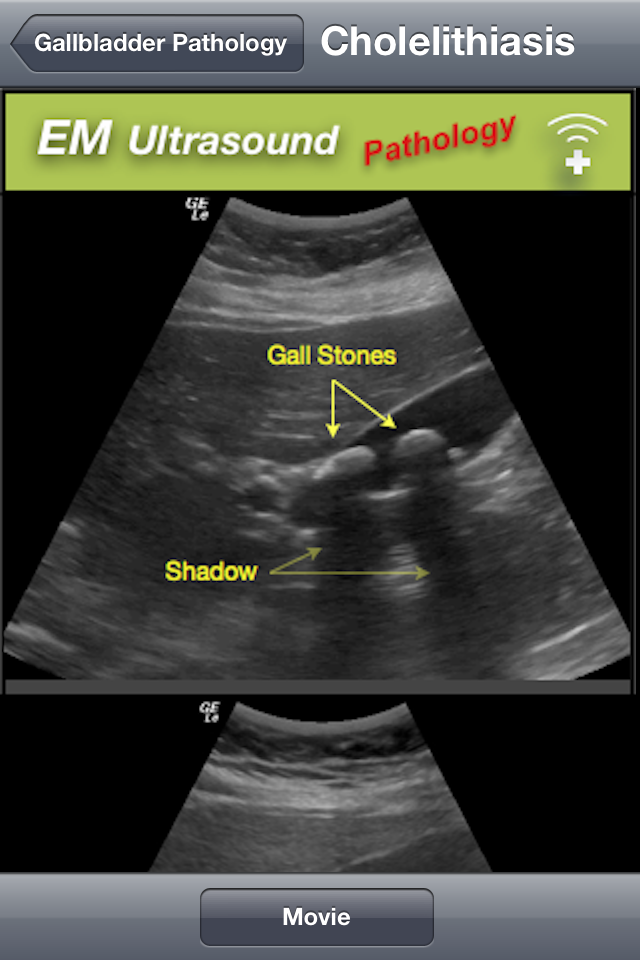

Ahora pasamos a la sección de escaneos, donde tenemos tambien, sus indicaciones, así como la tecnica para realizar el estudio, la anatomía normal, y las distintas patología que podemos diagnosticar usando la ultrasonografía.

Lo único que no me agrado de la aplicación es que, en lugar de tener su contenido en texto, son imágenes de no muy buena calidad, en cuanto al texto me refiero, ya que las imagenes de los ultrasonidos están muy entendibles y con sus respectivas anotaciones.